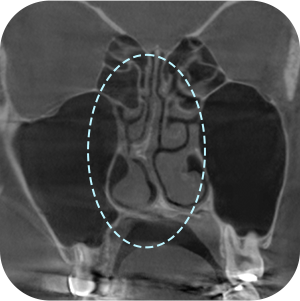

ตรจสอบผนังกั้นจมูก และโพรงจมูกภายใน

ตรจสอบตำแหน่งที่แน่นอน ของซิลิโคนเดิม

จำเป็นต้องถ่าย CT จมูกก่อนผ่าตัด ?

Aยิ่งเป็นกรณีผ่าตัดแก้ไข ก็ต้องยิ่งวิเคราะห์ละเอียดขึ้น!

การวิเคราะห์อย่างละเอียด จำเป็นอย่างมากต่อ การผ่าตัดแก้ไขจมูก

วิเคราะห์ได้อย่างละอียด

จากการถ่าย 3D-CT! - 03